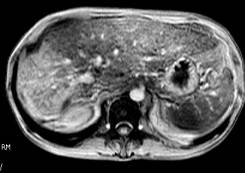

Bilan d'une cirrhose alcoolique après un épisode d'hépatite alcoolique aigue. Hypertrophie du lobe gauche, atrophie du lobe droit qui se rehausse de façon intense en phase artérielle. Persistance de plages interstitielles rehaussée sur les clichés à 10 mn.